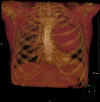

Giant thoracic mass: an unusual presentation of primary pulmonary Hodgkin's lymphoma

Primary pulmonary Hodgkin's lymphoma (PPHL) is rare. PPHL without peripheral lymphadenopathy or hepatosplenomegaly is exceptionally uncommon. We present a 61-year-old woman believed to have a solitary intrapulmonary fibrous tumour on a CT and a CT-guided biopsy, until surgical excision. Histopathology and immunohistochemistry of the excised mass confirmed PPHL. PPHL is a very rare differential diagnosis of large solitary intrapulmonary masses. A CT-guided biopsy is recommended, as it can be diagnostic, reserving excision for cases where the diagnosis remains in doubt.